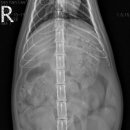

• 목련동물병원 | [목련동물병원] 고양이 자궁축농증 수술 케이스

경우 이러한 자궁축농증이나 유선종양 등의 질병을 예방하기 위해 중성화 수술을 해주시는 것을 권장드립니다. ​ 이상으로 고양이의 자궁축농증 수술 케이스 설명을 마칩니다. 감사합니다. ​ ​ ​ 목련동물병원 대구광역시 수성구 용학로 194 1층 ​ [ 목련동물병원 ] 주소 : 대구 수성구 용학로194 1층 문의 : 053-782-5475...

목련동물병원(2025-10-28 16:24:00)